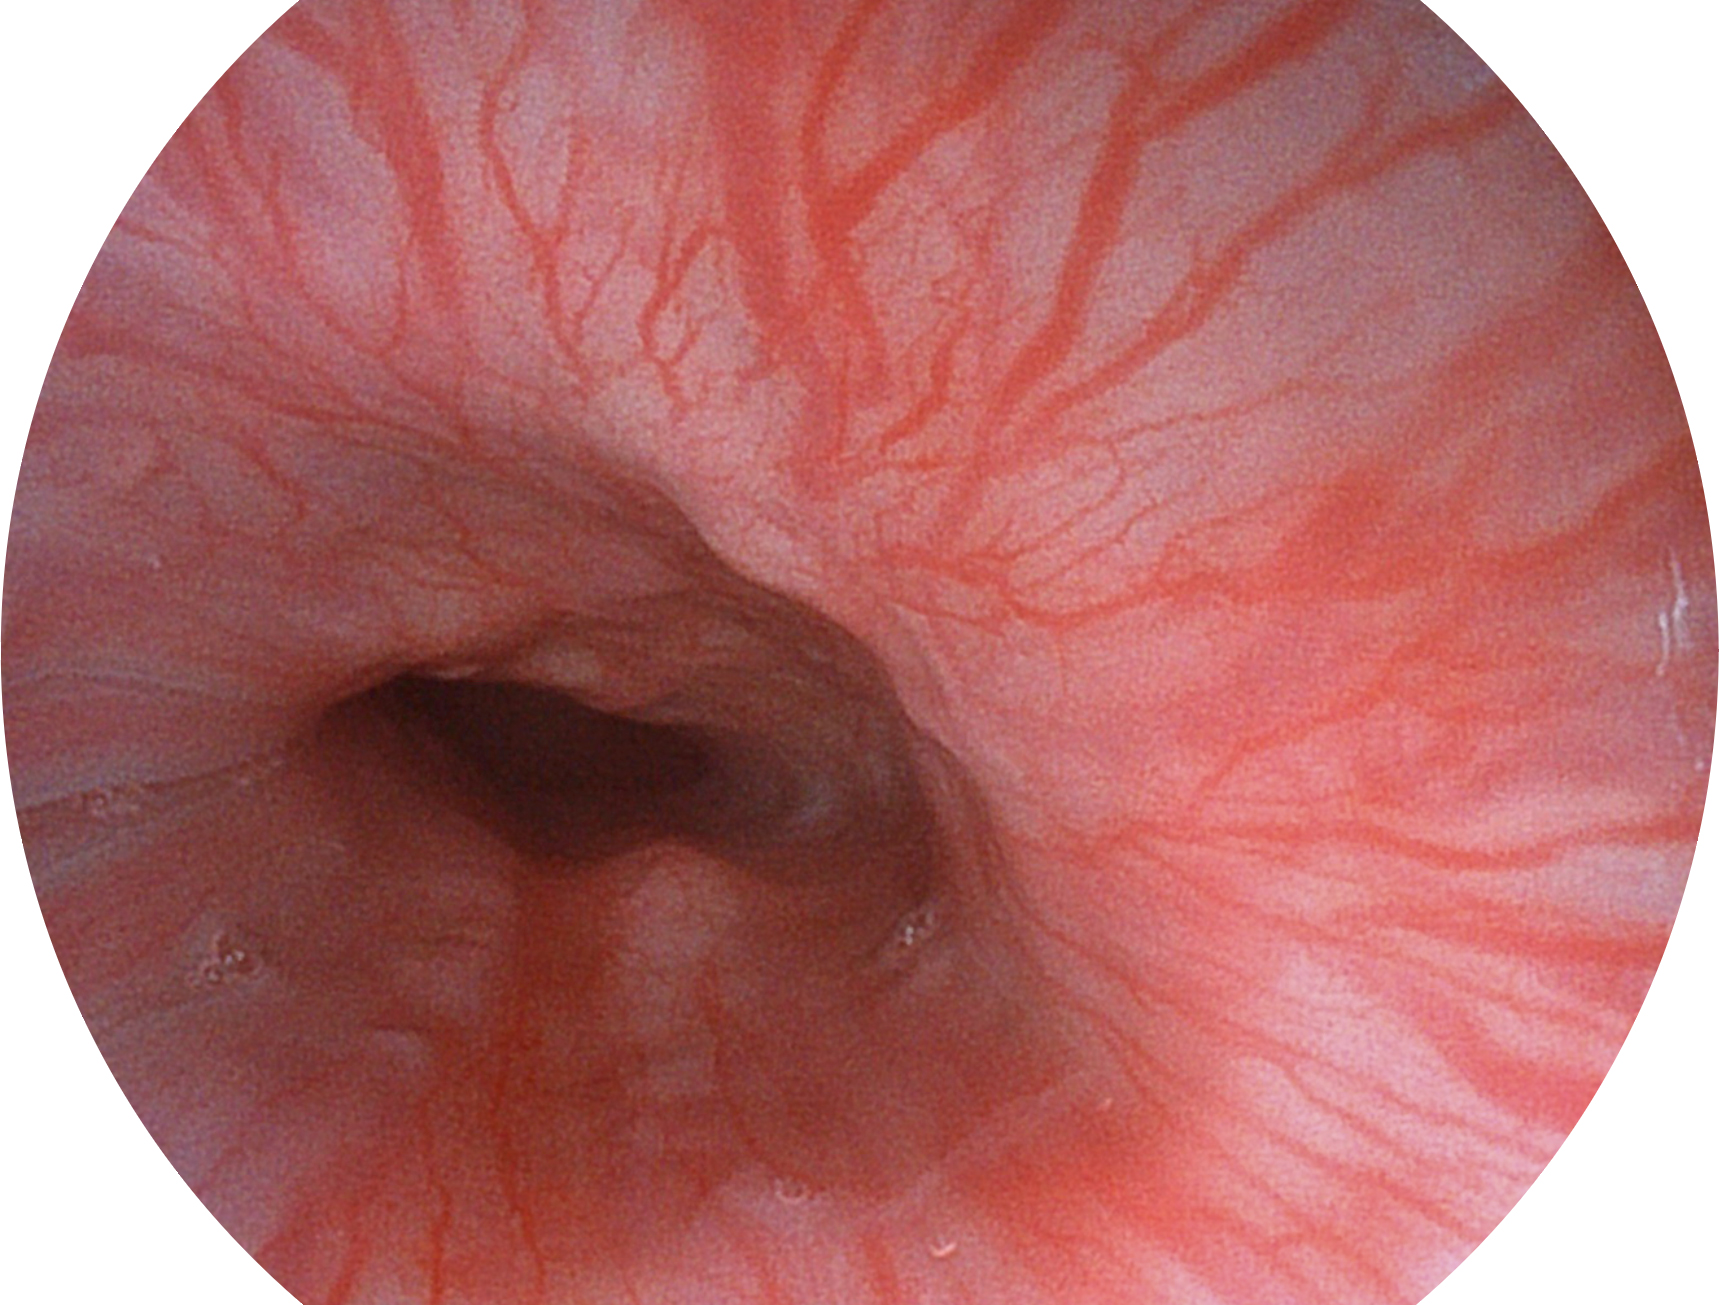

乐玩lewin国际新开发的内镜染色技术,主要是基于多波长LED 光源的开发,VLS-55Q 四波长LED 光源是由四个不同颜色的LED光按照相应照明模式所规定的特定发光比例进行合束后形成,合束后形成的照明光的光谱由红光、绿光、蓝光及蓝紫光这四个不同的波段范围构成。具有更高光谱自由度,通过光谱比例的控制,实现了聚谱成像技术,英文全称为“Spectral Focused Imaging, SFI”,缩写为“SFI”和光电复合染色成像技术,英文全称为“Versatile Intelligent Staining Technology, VIST”,缩写为“VIST”。